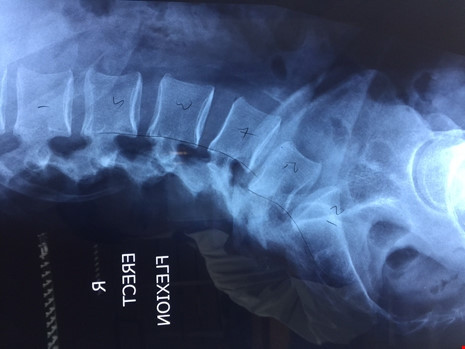

Hình ảnh chụp X-quang của bệnh nhân.

Khi thăm khám, các bác sĩ phát hiện trên phim X-quang có hình ảnh trượt đốt sống L4L5 độ 2 (trượt nặng), cột sống thoái hoá nghiêm trọng, xẹp toàn bộ chiều cao đĩa đệm L4L5, nhiều mổ xương thoái hoá mọc ra. Trên phim cộng hưởng từ có hình ảnh thoái hoá độ 5 đĩa đệm L4L5, thoát vị đĩa đệm L4L5 chèn ép vào rễ thần kinh L5 bên trái.